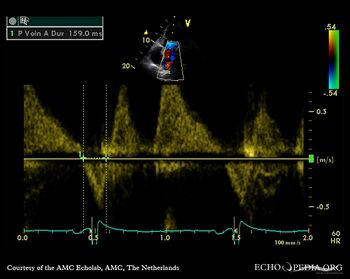

A3CH Pulsed-wave Doppler signal of mitral inflow: E>A

Pulsed-wave Doppler signal of mitral inflow Pulsed-wave Doppler signal of pulmonary venous flow: A